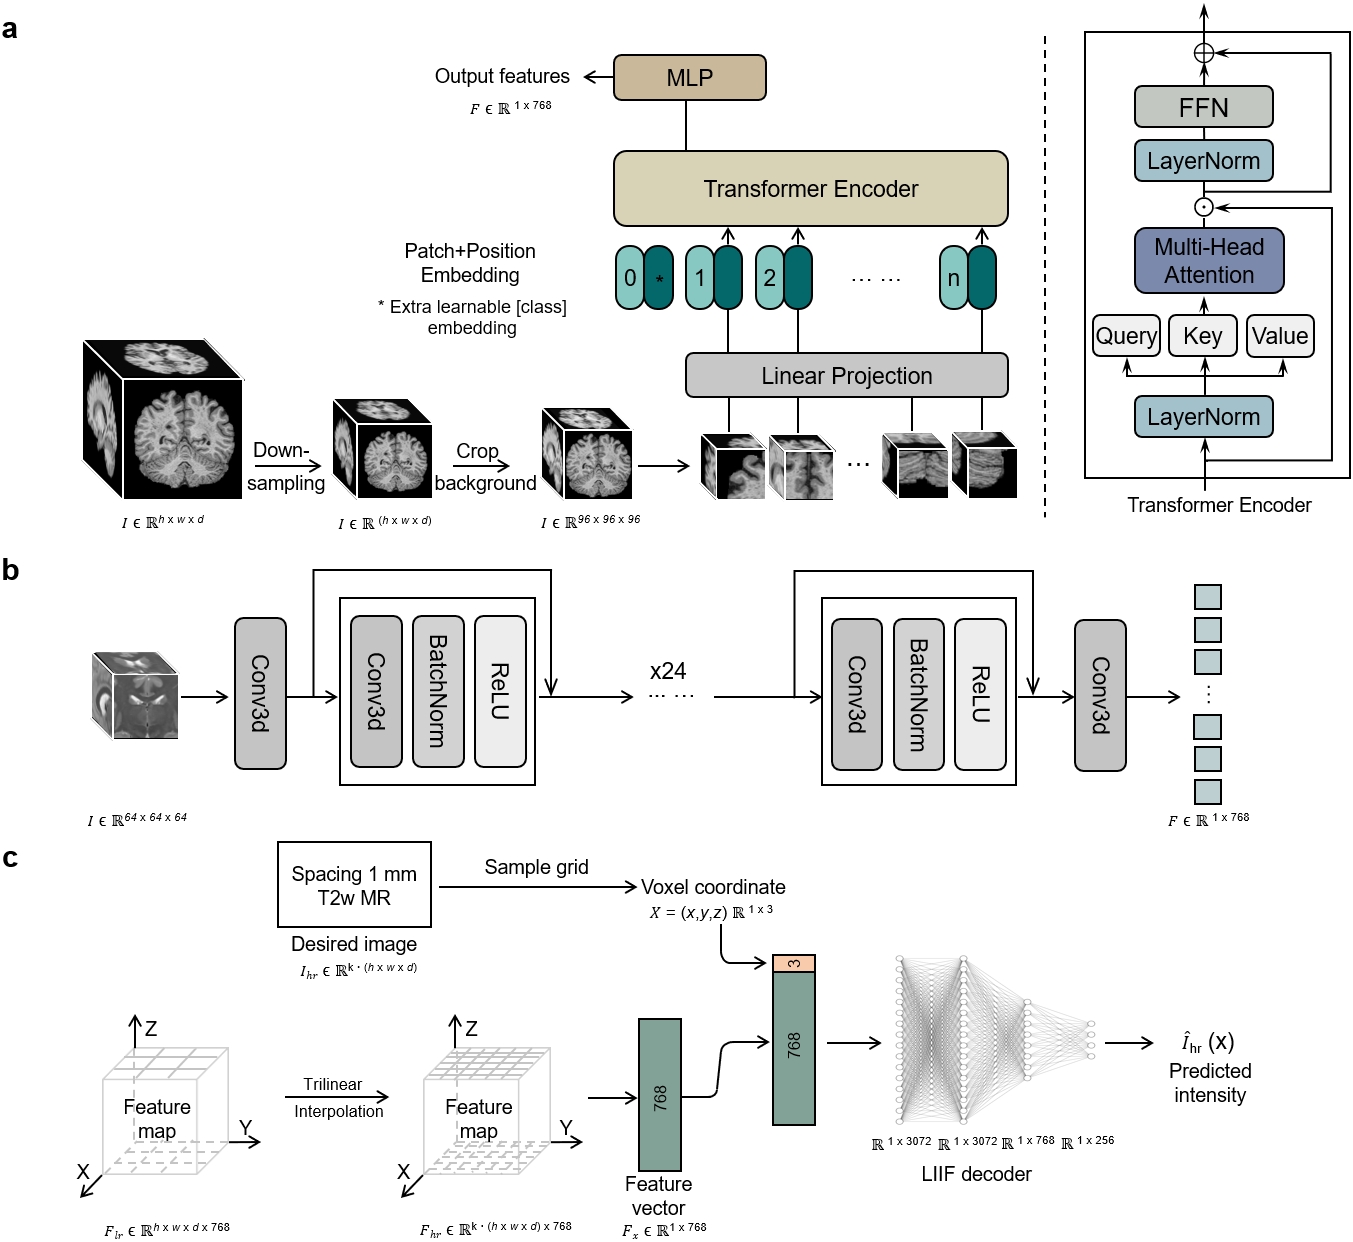

The overview of our work is shown in Fig.1. The goal of our work is to develop a universal synthesis framework for brain MR images, which can generate desired high-quality MR images according to practical demands provided by text prompts. To ensure the versatility and generalizability of our synthesis model, we collected a large-scale brain MR database with 31,407 3D image-text pairs from 13 datasets located in four continents, including 7 structural MRI modalities, spanning ages from 2 to 100+ years old, and covering a large spectrum of diseases and health conditions (Table 1). The text (metadata) includes subject information such as age and gender, as well as key MR imaging parameters, including scanning field strength, scanner type, voxel size, repetition time (TR), echo time (TE), inversion time (TI), and flip angle (FA). The designed English prompt integrates metadata as illustrated in Fig.1 b and c. To effectively align and fuse image-text pairs, our TUMSyn is built upon a two-stage training strategy. In the first stage, we pre-trained a text encoder using contrastive learning to effectively extract textual semantic features which are aligned with the corresponding image features from metadata (Fig.1 b). In Supplementary Fig.1 a and b, we evaluate the pre-trained text encoder by showing zero-shot performance on image-to-text retrieval. We can see that our text encoder accurately provides highly relevant textual descriptions for the given images, either producing complete prompts or solely imaging modality, indicating its ability to understand and master the semantic relationship between paired images and texts. More details are given in section “Description of experimental setup”.

Built on the pre-trained text encoder, in the second stage, the text encoder is frozen and used to extract prompt features to steer the cross-sequence synthesis. To enable MRI synthesis with desired spatial resolution, the fused text and image features are passed to a decoder, which supports super-resolution for continuous upsampling factor using Local Implicit Image Function (LIIF) [26]. In such way, our model, developed on large-scale datasets, can effectively generate target sequences with desired spatial resolution (Fig.1 c).

The model framework is demonstrated in Fig. 1 b and c, which contains two training stages: the language-image pre-training (shown in b) and the training of the image synthesis network (shown in c). More details are given below.

Image-text pre-training

The objective of the image-text pre-training model is to build cross-modal correspondences between visual content and linguistic semantics, which enables text-guided image synthesis for the follow-up image synthesis network. In this study, to align our text prompts and 3D volumes, we develop a domain-specific Brain MRI Language-Image Pre-training (BMLIP) model, including an image encoder and a text encoder, that can establish relationships between 3D brain MRI scans and their corresponding imaging parameters, namely scanning field strength, MR scanner model, voxel size, TR, TE, TI, and FA. The text encoder is capable of holding a text length of 90 tokens and is specific to characterizing brain MR imaging parameters. Due to the abundance of numerical and sequential information within the text prompts, we adopt the pre-trained Byte-Pair Encoding (BPE) tokenizer used in the original CLIP paper [22]. Compared to other tokenizers, the BPE tokenizer has superior adaptability across a wider range of datasets. <startoftext> and <endoftext> tokens are added at the beginning and the end of each text prompt to distinguish between different text prompts. Subsequently, the numerical sequences are passed into a text encoder to obtain text representations. Due to the richer content in our text prompt compared to the ones used in the original CLIP that only contains category information, we set the encoded length to 90 tokens. Inspired by the original CLIP, the text encoder is a Transformer with modified architecture [42]. As the image encoder, we utilize ViT-B/16 architecture as the backbone, where B represents the base model size consisting of 12 transformer layers and 12 attention heads with an embedding dimension of 768 and a hidden dimension of 3,072, and 16 denotes the token size of . Considering the critical importance of inter-slice structural information, we modify the network architecture, which is designed for 2D natural images, to accommodate 3D MR images. To manage the computational demands of 3D image computing, we downscale the entire input volume to of its original size (by half in each dimension) and further crop out the background to the size of 969696 (Extended Data Fig. 2 a).

Image synthesis network

The image synthesis network is designed to generate target MR images from the available images steered by the text prompts. This network comprises four key components including an image encoder, a text encoder, a multi-modality cross-attention module, and an implicit decoder (Fig. 1 c). Concerning memory limitation, we cut volume into image patches with size of voxels as input of the image encoder. Initially, the image patches and text prompts are encoded into features through their respective encoders. It should be noted that the text encoder is pretrained and frozen in this stage, while the image encoder is trained on a larger backbone. Specifically, the image encoder (Extended Data Fig. 2 b) is built on the24-layer ResNet architecture, omitting downsampling operation to preserve the original resolution of the anatomical structure of brain regions. The image encoder maintains a hidden dimension of 256 in its resblocks, and ultimately projects to a 768-dimensional feature space via a convolution layer. The text features are fed into a text adapter, which consists of a fully connected layer and a rectified linear unit (ReLU) that adapts the features from the frozen text encoder to the image synthesis task. The extracted image and text features are then passed to a cross-attention module, which follows the standard multi-head self-attention architecture. In particularly, the text embeddings serve as the Query and image embeddings serve as the Key and Value. The cross-attention module integrates embeddings of both text and image modalities and generates the target image features controlled by the text prompts.

The image decoder aims to achieve arbitrary-scale upsampling (Extended Data Fig. 2 c). Here, we adopted the LIIF which represents images as continuous functions rather than discrete pixels. Specifically, the image decoder takes the LR image feature maps from cross-attention module as a grid of feature vectors. Each feature vector corresponds to a voxel at the coordinate X in the original image. For any given coordinate in the continuous image space, LIIF identifies the nearest feature vectors from the grid and performs interpolation according to the upscaling factor to generate a location-aware feature vector. This interpolated feature vector, along with the corresponding target coordinates, is then fed into LIIF decoder to predict the pixel value at that specific location. The LIIF decoder is constructed with four linear layers, with embedding dimensions of 3072, 3072, 768, and 256, respectively. The output of the decoder is ultimately a resolution-enhanced brain MR image guided by prompt-specified imaging sequence.